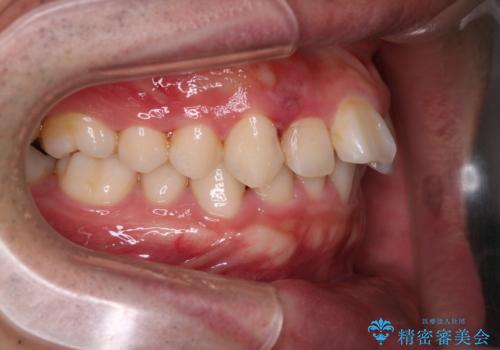

- 前歯が出ていることを主訴に来院されました。

歯列の幅が狭かったため、横に広げながらスペースを作り、叢生の改善を行いました。

左側の犬歯関係も治療前より良い状態で治療を完了することができました。

今回は臼歯部の遠心移動を行うために2級ゴムを使用しています。